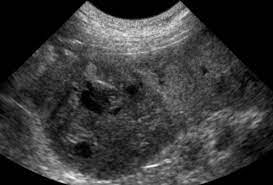

Cancer Tumors Of The Spleen Bluepearl Pet Hospital from bluepearlvet.com Mast cell tumor dogs often will have a lump on the skin that can look or feel like almost anything.; In some cases, one cause for the enlargement and inflammation of the spleen is a condition known as eosinophilic gastroenteritis. It's rare for a dog owner to even know the tumor is there until it ruptures. It is a cancer made up of the cells that line blood vessels, and therefore can be found in any part of the body. Dog mast cell tumors are one of the most common forms of dog skin cancer. Your options for splenic hemagiosarcoma. Causes of spleen tumor in dogs even though the first reports of canine hsa go back as far as 1960s, the exact cause of the spleen tumor in dogs is still unknown (12, 13, 14). Cancer can also cause dogs to lose weight while maintaining their regular appetite.

This cancer metastasizes at a rapid rate and affected dogs have limited survival time. Many other types of tumors, both benign and malignant, can occur in the spleen. Because of this, the tumor can rupture, leading to sudden and severe hemorrhage, collapse, and rapid death. It is the tumor of cells that line blood vessels, but most commonly affects heart, spleen, liver or skin. The spleen is an organ that will store blood and will also supply blood to other organs, while cleaning blood cells as well. Spleen and liver hemangiosarcoma in dogs. In some cases, one cause for the enlargement and inflammation of the spleen is a condition known as eosinophilic gastroenteritis. Hemangiosarcomas are fed by the blood vessels and fill with blood. Dogs with hemangiosarcoma in the spleen may not show any symptoms at the early stage. These causes include splenic torsion due to torsion causing the blood flow to be cut off, acute canine infectious hepatitis, salmonellosis and some types of spleen cancer (splenic lymphoma, splenic hemangiosarcoma). In this condition, cells and other substances from other parts of the body start to infiltrate into the spleen and cause an enlargement. This cancer is typically diagnosed via fine needle aspiration. If you notice your dog shedding pounds, either rapidly or slowly, make an appointment with your vet.

Https Encrypted Tbn0 Gstatic Com Images Q Tbn And9gctpw20aphku0gx0zqpgwvoc63jjsswrygculgbl Vkqndualo Usqp Cau from Lymphoma is a type of cancer that affects the lymphatic system. Cancer can also cause dogs to lose weight while maintaining their regular appetite. If you notice your dog shedding pounds, either rapidly or slowly, make an appointment with your vet. Mast cell tumors most commonly form nodules or masses in the skin, they can also affect other areas of the body, including the spleen, liver, intestine, and bone marrow. Spleen cancer occurs rarely in dogs and the causes of this disease are not entirely known. There are two main types of canine spleen cancer, hemangiomas and hemangiosarcomas. In dogs, the common primary sites for hemangiosarcoma are the spleen, the right atrium of the heart, and the subcutis, which is the tissue beneath the skin. This form of cancer is most common in the german shepherd, golden retriever and other large breeds.

Liver Cancer In Dogs Signs Symtoms Causes Huntersville Vet Carolina Veterinary Specialists from d2zp5xs5cp8zlg.cloudfront.net Causes of spleen tumor in dogs even though the first reports of canine hsa go back as far as 1960s, the exact cause of the spleen tumor in dogs is still unknown (12, 13, 14). It is a cancer made up of the cells that line blood vessels, and therefore can be found in any part of the body. In dogs, red blood cells are the actual source of spleen cancer. Abdominal cancer can be a silent killer because dogs don't usually show any signs of illness by the time it might be too late. This cancer is typically diagnosed via fine needle aspiration. Many dogs will experience enlargement of the lymph nodes in one or more parts of the body. A mast cell tumor (mct) is a type of tumor consisting of mast cells. It is the tumor of cells that line blood vessels, but most commonly affects heart, spleen, liver or skin.

It is the tumor of cells that line blood vessels, but most commonly affects heart, spleen, liver or skin. Spleen and liver hemangiosarcoma in dogs. This is one of the most dangerous tumors in dogs. Many dogs will experience enlargement of the lymph nodes in one or more parts of the body. It is a cancer made up of the cells that line blood vessels, and therefore can be found in any part of the body. Often, owners do not realize their dog is affected until the sudden hemorrhage or collapse. If the above describes your dog's situation, then the immediate option is surgery. Sometimes this cancer may cause weakness, especially in the hind legs, and decreased energy that lasts for a day or two, then goes away only to reappear weeks or months later. In both cases, the mass forms out of the soft tissue creating what looks a lot like a blood blister. Cancer can also cause dogs to lose weight while maintaining their regular appetite. This cancer metastasizes at a rapid rate and affected dogs have limited survival time. In dogs, red blood cells are the actual source of spleen cancer. Hemangiosarcomas are fed by the blood vessels and fill with blood.